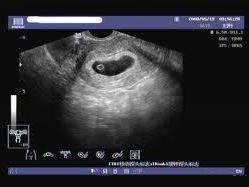

空孕囊是指孕婦在妊娠早期,胚胎發(fā)育異常或停止發(fā)育,導(dǎo)致孕囊內(nèi)沒(méi)有胚芽或胎心的情況,對(duì)于期待寶寶的家庭來(lái)說(shuō),空孕囊的出現(xiàn)無(wú)疑是一種打擊,了解空孕囊的征兆,早期識(shí)別并采取措施,對(duì)保障母嬰健康具有重要意義,本文將為您詳細(xì)解析空孕囊的十個(gè)征兆,以便您及時(shí)察覺(jué)并處理。

通過(guò)B超檢查發(fā)現(xiàn)胚胎未按照正常時(shí)間發(fā)育,如未按時(shí)出現(xiàn)胚芽、胎心等,可能是空孕囊的表現(xiàn)。